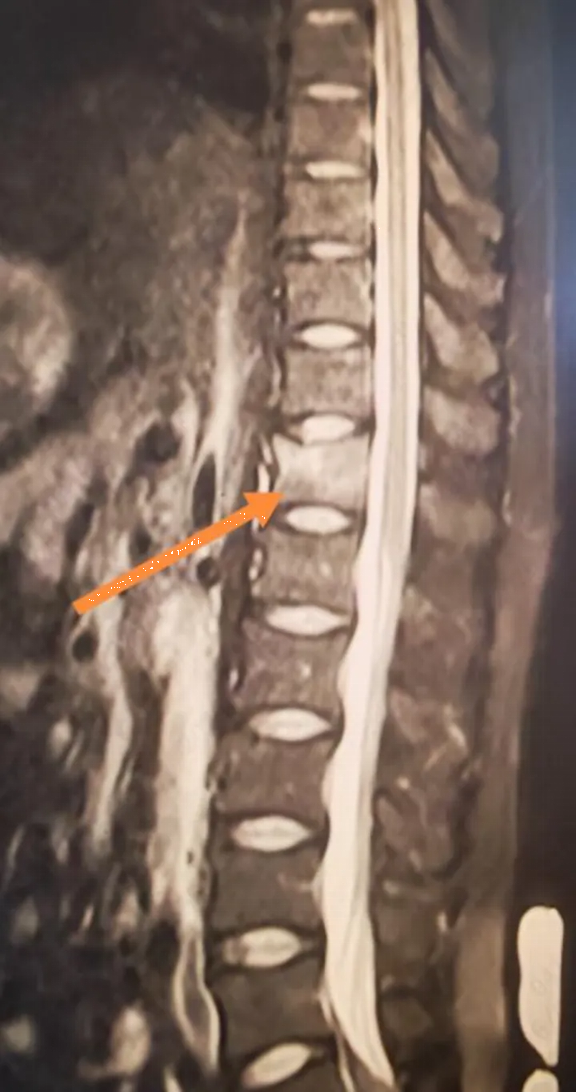

Sau khi khám kỹ, bác sĩ kết luận rằng anh Lý rất có thể bị gãy xẹp đốt sống. "Chắc chắn là có nhầm lẫn rồi! Tôi tập thể dục thường xuyên, xương khớp của tôi rất tốt, làm sao tôi có thể bị gãy xương chỉ vì nâng một quả tạ nhẹ chứ?". Anh Lý cảm thấy chẩn đoán của bác sĩ có vẻ hơi phóng đại. Chỉ sau khi được bác sĩ thuyết phục kiên nhẫn, anh LÝ mới miễn cưỡng đi chụp MRI.

Kết quả chụp MRI khiến anh hoàn toàn sững sờ: gãy xẹp đốt sống T12.

Các xét nghiệm tiếp theo cho thấy kết quả còn gây sốc hơn chỉ số Z-score L1-L4 của anh Lý chỉ là -3,1, nghĩa là mật độ xương của anh thấp hơn so với hầu hết phụ nữ 60 tuổi. Một loạt các xét nghiệm đã loại trừ khả năng loãng xương thứ phát. Kết quả xét nghiệm cho thấy nồng độ vitamin D của anh Lý chỉ ở mức 10 ng/ml, thấp hơn nhiều so với tiêu chuẩn bình thường.